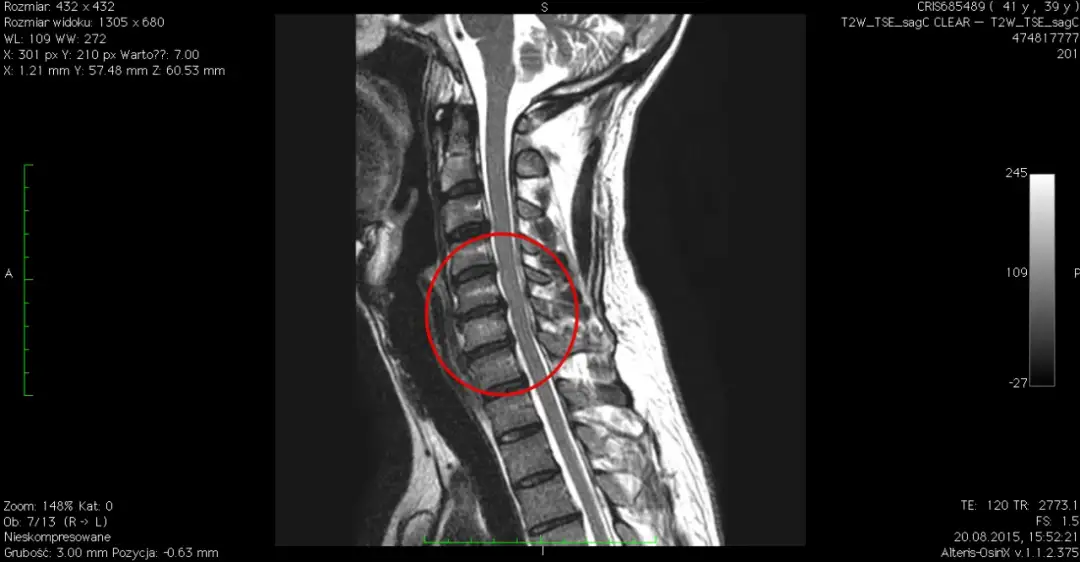

Poznaj objawy i metody leczenia choroby krążka międzykręgowego szyjnego z uszkodzeniem nerwów rdzeniowych. Dowiedz się, jak rozpoznać dyskopatię szyjną i zapobiegać powikłaniom.